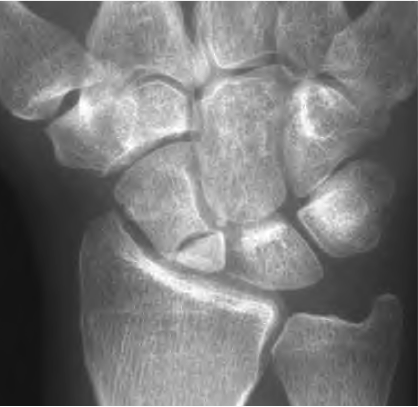

עצם הסירה או העצם הנביקולרית הינה עצם חשובה בשורש כף היד. שורש כף היד מורכב משמונה עצמות קטנות המסודרות בשתי שורות. עצם הסירה היא העצם התחתונה בצד האגודל. כאשר אנשים נופלים עם שורש כף היד פרוש, הם עלולים לשבור את עצמות האגודל. אחד הקשיים הוא באבחנה, שכן בצילומי רנטגן ראשוניים הכל נראה תקין.

לעתים, כאשר ישנו כאב באזור המכונה "תיבת ההרחה", גם אם הכל נראה תקין בצילומי הרנטגן שורש כף היד יקובע ויבוצעו צילומי רנטגן חוזרים, עד שיהיה ניתן לבצע אבחנה חד משמעית.

צילומי רנטגן חוזרים נעשים לרוב 10-14 ימים לאחר הפציעה. לרוב, השילוב של בדיקה וצילומי רנטגן יכול לקבוע בוודאות האם ישנו שבר. אם ישנו עדיין ספק, שורש כף היד יעבור צילום רנטגן נוסף שבועיים לאחר מכן, או שיבוצעו בדיקות נוספות כגון סריקת עצם, CT או MRI.

לעצם האגודל יש מוניטין של "עושה צרות". לעתים היא פשוט לא רוצה להרפא! דבר זה הינו בחלקו תוצאה של אספקת דם בלתי מספקת לחלק התחתון או הקרוב של העצם. זוהי הסיבה העיקרית לכך שיש לקבע את שורש כף היד גם כאשר האבחנה אינה וודאית. הטיפול צריך להתחיל מיד, וגם עיכוב של מספר שבועות יכול למנוע מהעצם להחלים.